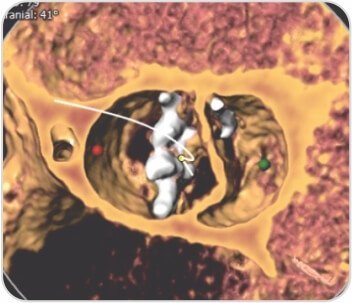

سيدة تبلغ من العمر 66 عامًا، تعاني من ارتفاع ضغط الدم، وتم تقييم ضيق التنفس الجهدي من الدرجة الثانية وتبين أنها مصابة بتضيق شديد في الأبهر، Sievers 0 bicuspid. كشف CAG عن الشرايين التاجية الطبيعية. تم إجراء عملية TAVI بنجاح تحت التخدير الواعي باستخدام جهاز Evolute R الممتد ذاتيًا مقاس 23 مم دون أي مضاعفات.